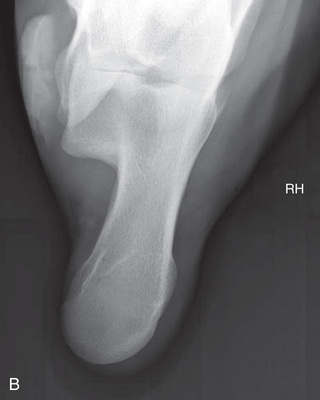

Digit/foot: P-III (distal phalanx, coffin bone) P-II (middle phalanx) P-I (proximal phalanx-pastern) Proximal interphalangeal joint (pastern joint) joint | DP (Standard) (Fig. 24.62B,C) | Dorsal 45-degree proximal–palmarodistal (D45Pr-PaDi) | Foot slightly forward on image receptor. | Perpendicular to foot axis at MSP (midsagittal plane) at area of interest with beam angled ~45 degrees to ground |

| Lateral (Standard) (Fig. 24.62D) | Lateromedial | On a block to elevate limb for P-III; resting on ground for other views. | 90 degrees lateral to MSP, parallel to ground on area of interest: coronary band for PIII | |

| Lateral-interdigit (Optional) | Lateromedial (mediolateral) with interdigital film | Receptor between digits. Easiest with patient in lateral recumbency but can be completed standing with foot raised. | 90 degrees laterally from MSP to radiograph the lateral claw. 90 degrees medially from MSP medially to radiograph the medial claw. | |